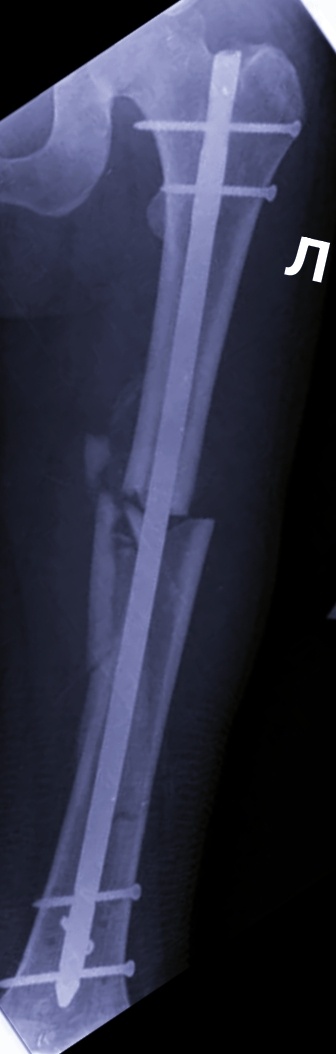

После внешней репозиции аппаратом фиксации теперь должны были установить интрамедуллярный стержень в бедренную кость( остеосинтез). Что ж, операция знакомая, хирурги опытные, по времени часов до одиннадцати управимся.

Собрала свой аппарат, подкатила в нужное место, начали делать доступ в бедро сначала, а мое дело снимать, как заходит гвоздь, как собираются отломки кости на этот гвоздь. Ну, шикарно просто собрали.

Тем временем хирурги через аккуратные надрезы уже заводили и закручивали винты: блокирующие и кортикальные.

Два винта после снимков перекрутили, им не понравилось, как изначально они " встали".